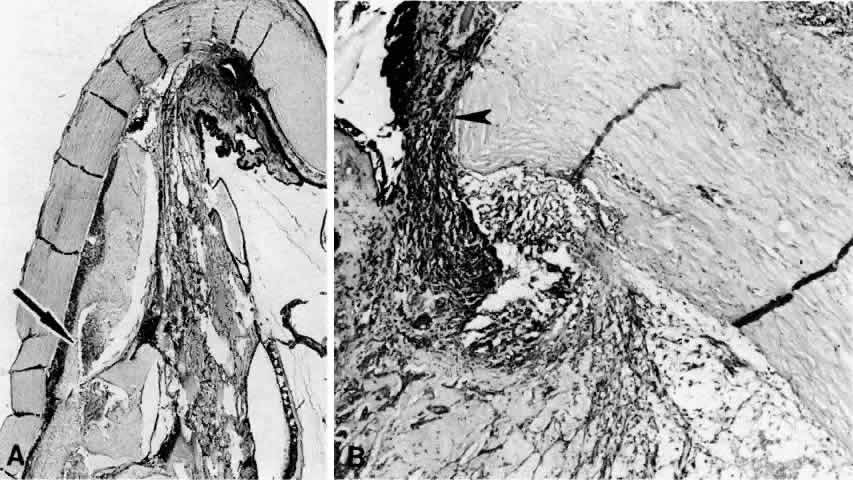

Various surgical procedures may be complicated by a ciliochoroidal effusion during or after the procedure. An expulsive effusion can mimic an expulsive hemorrhage during cataract extraction33–36 or glaucoma surgery, especially in patients with prominent preoperative episcleral vessels, as in Sturge-Weber syndrome.37 Varying degrees of postoperative suprachoroidal edema may develop after cataract extraction (Figs. 7 and 8),1,9,32–34,38–46 iridectomy (Fig. 9), filtering procedures (Fig. 10),1,9,32,37,47–49 retinal detachment surgery (Fig. 11),50–54 panretinal photocoagulation,55,56,56a or cryotherapy. A postoperative ciliochoroidal effusion can occur weeks, months, or even years after surgery.40,57 Between 1 and 18 months after filtration surgery, hypotony and ciliochoroidal detachment developed in four patients when timolol or acetazolamide therapy was instituted.57

Fig. 8. This choroidal and ciliary body detachment, which occurred after intracapsular cataract extraction, was mistaken for a malignant melanoma.39 A. Iris incarceration in the wound (arrow) and extensive ciliary body effusion consisting of a dense, proteinaceous material (asterisk) (H & E, × 115). B. Effusion of the choroid near the ora serrata by a moderately dense, proteinaceous material without inflammatory cells. Note folds of choroid (arrowheads) (H & E, × 115).